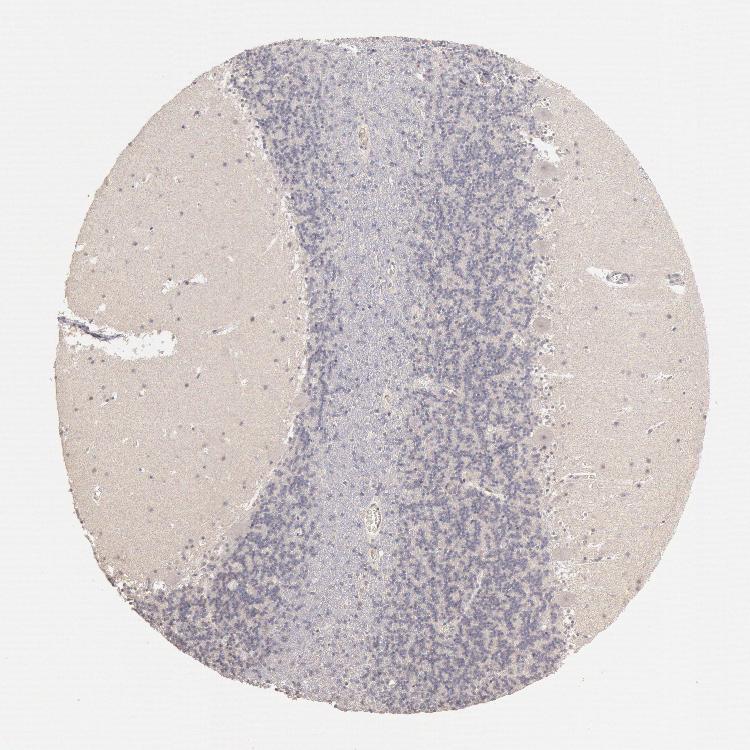

CEREBELLUM - Antibody stainingi

Antibody staining in the annotated cell types in the current human tissue is reported as not detected, low, medium, or high, based on conventional immunohistochemistry profiling in selected tissues. This score is based on the combination of the staining intensity and fraction of stained cells.

Each image is clickable and will lead to virtual microscopy that enables deeper exploration of all samples and also displays staining intensity scores, fraction scores and subcellular localization as well as patient and tissue information for each sample.

Antibody HPA001301

Purkinje cells Not detected

Cells in granular layer Not detected

Cells in molecular layer Not detected